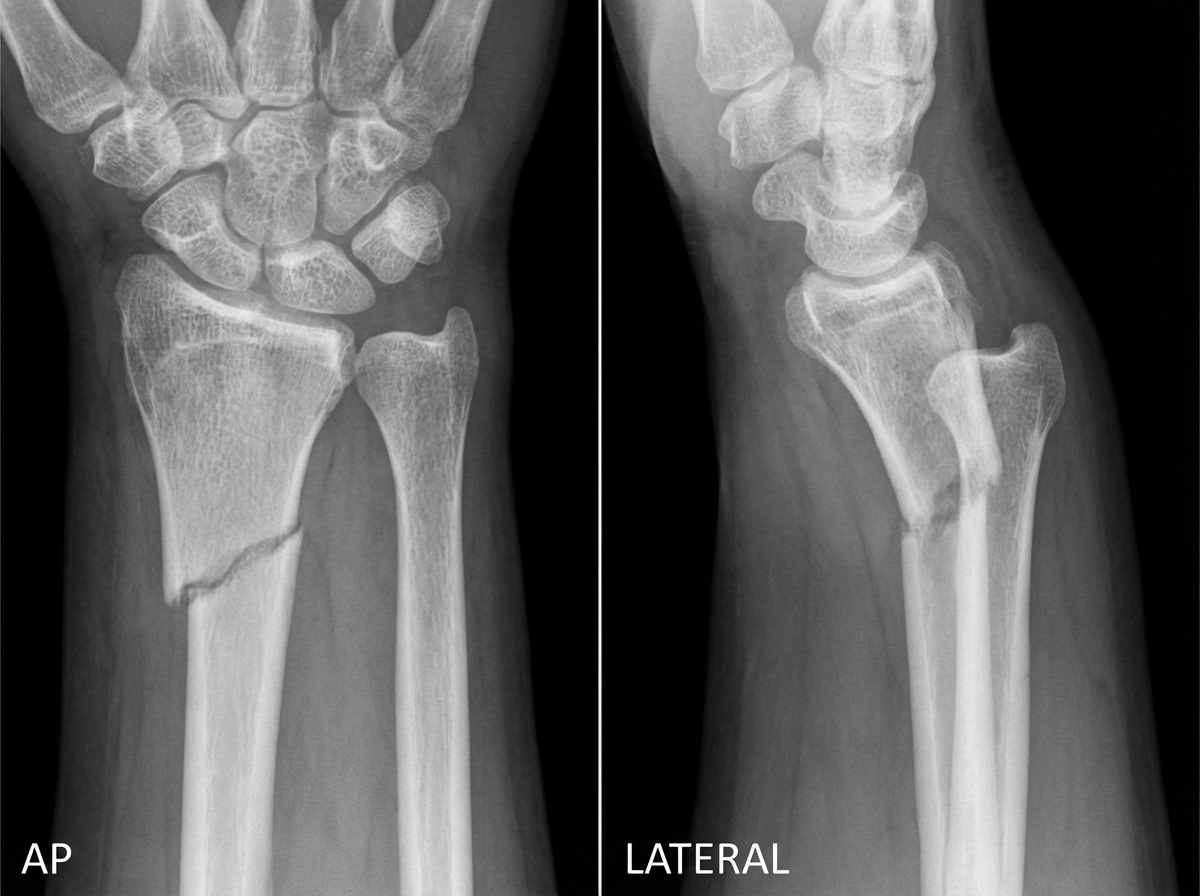

AP and lateral views of the wrist are provided. What is the diagnosis?

Explanation: ***Galeazzi fracture*** - Characterized by a **fracture of the distal third of the radius** with **dislocation of the distal radioulnar joint (DRUJ)**. - **Mnemonic**: "**GRU**" - **G**aleazzi involves **R**adial fracture with **U**lnar dislocation at the wrist. *Monteggia fracture* - Involves **fracture of the ulnar shaft** with **dislocation of the radial head** at the elbow. - **Mnemonic**: "**MURL**" - **M**onteggia involves **U**lnar fracture with **R**adial dislocation at the e**L**bow. *Smith fracture* - **Volarly angulated distal radius fracture** (reverse of Colles), often called "**reverse Colles fracture**". - Results from **flexion mechanism** and shows **volar displacement** of the distal fragment on lateral view. *Colles fracture* - **Dorsally angulated distal radius fracture** with **dorsal displacement** of the distal fragment. - Shows classic **dinner fork deformity** clinically and **dorsal angulation** on lateral X-ray view.